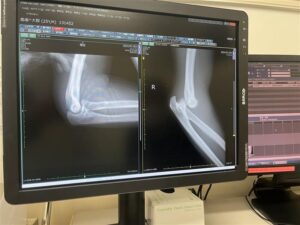

3年目は年明け早々に肘の脱臼。

この時はわりと激しく転倒し、後続車に遊ばれてしまいました。

以前もブログでも紹介しましたが唯一プロテクターの無い箇所の怪我でした。

プロテクターの重要性を我が身をもって体験できたのはいい経験だったと思います。